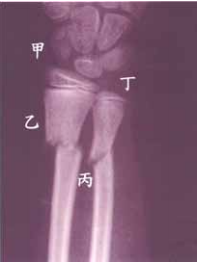

54 7 歲男童小軒於公園玩耍,自鞦韆上跌落,導致左前臂骨折如圖所示。於整復時必須加用分骨墊配合夾板來固定骨折,則分骨墊放置之位置應為何?

(A)甲(B)乙(C)丙(D)丁